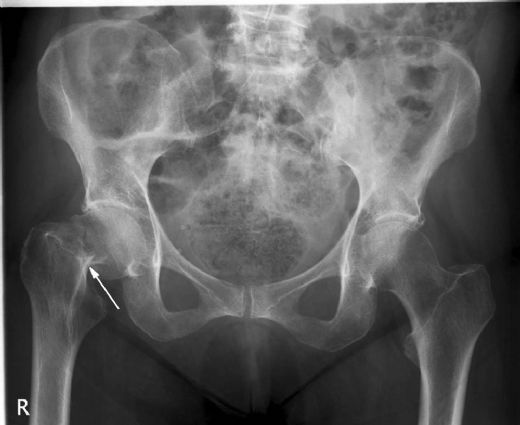

Kalça Kemiği Kırığı Teşhisi Kalça kemiği kırığı teşhisi genellikle klinik muayene ve görüntüleme yöntemleriyle konulur. Doktor, hastanın tıbbi geçmişini alır ve fiziksel muayene yapar. Ayrıca, kırığın yerini ve tipini belirlemek için genellikle aşağıdaki görüntüleme yöntemleri kullanılır:

Kalça kemiği kırığı, genellikle yaşlı bireylerde düşme gibi travmatik olaylar sonucunda meydana gelen ciddi bir yaralanmadır. Bu tür kırıklar, kalça eklemi etrafındaki femur başı veya femur boynu gibi bölgelerde oluşabilir. Kalça kemiği kırıkları, ciddi komplikasyonlar ve uzun süreli sağlık sorunlarına yol açabileceğinden, doğru bir şekilde teşhis edilmesi ve tedavi edilmesi son derece önemlidir. Kalça Kemiği Kırığının Belirtileri Kalça kemiği kırığının belirtileri genellikle aşağıdaki gibi sıralanabilir: